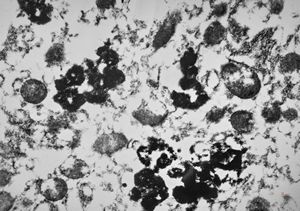

M,66y. | siderosomes

M,66y. | hemosiderin - siderosomes